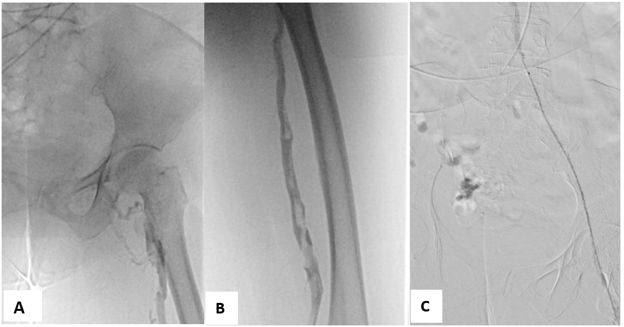

Hình 1: Hội chứng May–Thurner trên chụp tĩnh mạch đồ và siêu âm nội mạch2

(A) Chụp tĩnh mạch xâm lấn chi dưới trái cho thấy động mạch chậu chung phải chèn ép tĩnh mạch chậu chung trái, kèm tuần hoàn bàng hệ; (B) Siêu âm nội mạch xác nhận tình trạng hẹp tĩnh mạch chậu trái.

Ngoài ra, IVUS còn giúp định vị chính xác dây dẫn (guidewire) trong các tình huống tái thông mạch, đặc biệt khi tồn tại nhiều tuần hoàn bàng hệ quanh tĩnh mạch8. IVUS đặc biệt hữu ích trong việc đo diện tích và đường kính lòng tĩnh mạch chậu, những thông số quan trọng giúp lựa chọn kích thước và chiều dài stent phù hợp, từ đó giảm nguy cơ di lệch stent. Cuối cùng, IVUS còn hỗ trợ đặt stent chính xác hơn thông qua việc xác định rõ hợp lưu tĩnh mạch chậu, giúp hạn chế nguy cơ stent che lấp tĩnh mạch chậu chung phải8.

Hình 2: Chụp tĩnh mạch xâm lấn sau đặt stent2

Hình ảnh cho thấy tái thông hoàn toàn tĩnh mạch chậu chung trái; IVUS xác nhận tái thông lòng mạch và stent áp sát tốt.